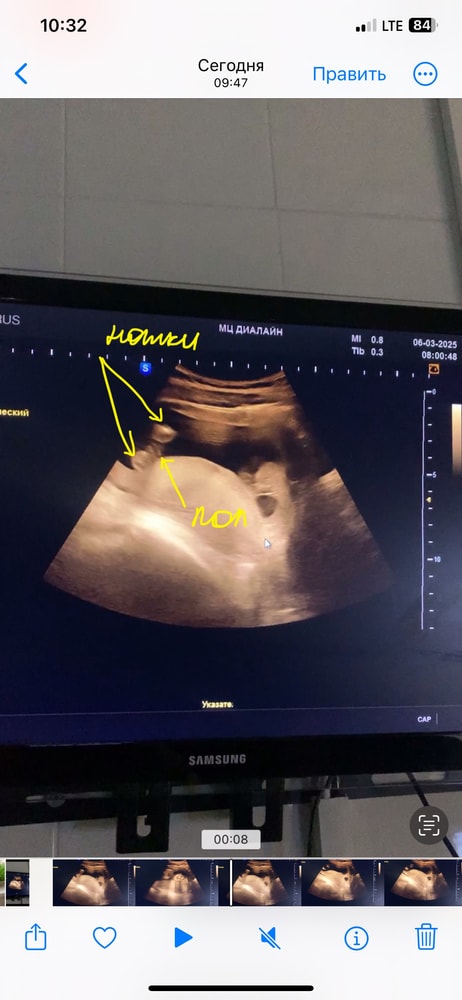

Как бы вы не хотели девочку-на фото мальчик😁

Алина, и ниже у вас на фото это не нога, а яйца. А выше палочка сами знаете что

Антонина, это мальчик, поверьте, я столько этих яиц перевидела. Из этой пи.пи.ськи пирожка не получится. У девочек не торчит ничего, а кофейное зернышко только между ног, сбоку вы у девочки не увидите ничего. А у вашего торчит

Пирожочек по-другому выглядит, сверху ничего не торчит, а снизу как кофейное зернышко